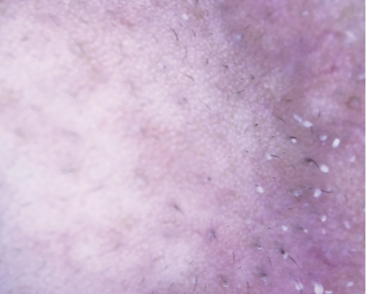

Do Not Be Fooled By This Acne Look-Alike

Diagnosing Demodex Follicular Overgrowth

Demodex follicular overgrowth is a mimicker of comedonal acne, appearing clinically non-inflammatory and localized on the chin. It is independent of blepharitis, rosacea, and acne vulgaris. Demodex follicular overgrowth does not respond to topical retinoids. While the Demodex mite is found in the pilosebaceous unit of most people, in this condition, the mites proliferate in excess and cannot fit within the hair follicle. Demodex mites protrude outside of the follicle, resembling closed comedones. Skin examination with a dermatoscope clearly distinguishes demodex overgrowth from comedones. Topical ivermectin cream 1% applied daily for a few days resolves the problem. Alternative treatments include topical sulfur, permethrin 5% cream, oral ivermectin, and oral metronidazole.